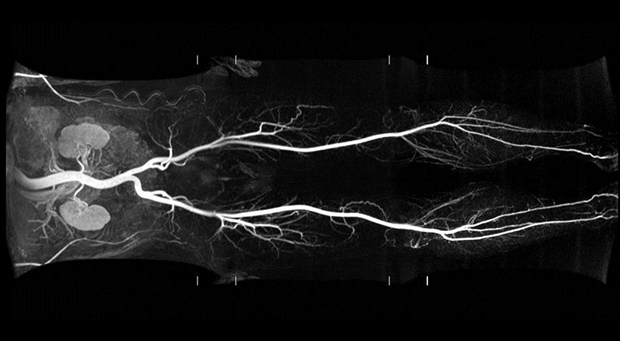

En la actualidad La Resonancia Magnética es una técnica de imagen que permite en un solo estudio, evaluar la morfología del corazón, los grandes vasos y las estructuras mediastinales adyacentes y además analizar y cuantificar la función cardiaca global y regional de forma inocua y reproducible. Esta información cuantitativa tiene una gran importancia pues permite determinar en forma objetiva los efectos del tratamiento médico o quirúrgico. Constituye una importante herramienta diagnóstica, no invasiva, y con una alta calidad de diagnostico.

Además de su óptima definición estructural, aporta datos que permiten una cierta caracterización del tejido y una información simultánea sobre la función y la viabilidad cardiacas. Por otra parte, en combinación con una provocación farmacológica con sustancias vasodilatadoras o inotrópicas, la RMC permite diagnosticar la isquemia. La RMC de estrés se utiliza de manera creciente para el diagnóstico y la valoración de la isquemia y la viabilidad miocárdicas, y proporciona una evaluación segura y efectiva de los pacientes con enfermedad coronaria

Evaluación funcional y anatómica

Mediante secuencias morfológicas (spin echo) y funcionales de cine-RM (gradient echo), proporciona información precisa acerca de:

-Dimensiones de cavidades cardiacas

– Grosor parietal

– Masa ventricular

– Volúmenes

– Función sistólica ventricular, global y segmentaria.

– Funcion diastolica.